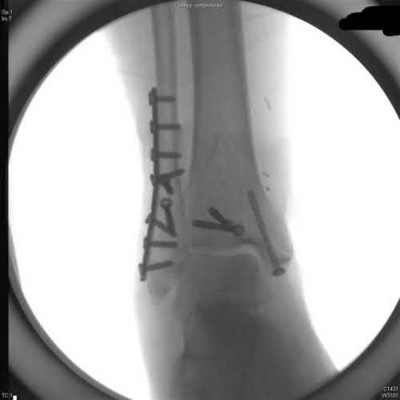

A 25-year-old female is involved in a motor vehicle collision. She presents with the isolated injury seen in Figures A through D. Her leg is swollen but her skin is intact. She has no clinical signs of compartment syndrome. Which of the following treatment options will allow for maintenance of fracture alignment and minimize the risk of soft tissue complications?

The patient presents with a closed distal third metaphyseal-diaphyseal distal tibia fracture with simple intra-articular extension. Immediate intramedullary nailing along with percutaneous fixation of the articular component provides appropriate restoration of length, rotation and alignment and minimizes the risk of wound complication.

Displaced distal third tibia fractures may be associated with simple intraarticular extension. Operative treatment of intra-articular distal tibia fractures has historically been performed with open reduction and internal fixation. Early open reduction and plate fixation of pilon fractures has been associated with high rates of infection and wound complication. In select patterns with simple articular extension, percutaneous screw fixation and medullary nailing may provide appropriate reduction with minimal soft-tissue risk.

Marcus et al. evaluated the outcomes of immediate intramedullary nailing and percutaneous fixation of simple intra-articular distal tibia fractures (AO/OTA 43 C1 and C2). The authors found excellent rates of union and alignment, however caution against broad application of this technique until more rigorous randomized studies can be performed.

Sirkin et al. retrospectively evaluated the results of a staged approach to management of intra-articular distal tibia fractures with temporary bridging external fixation followed by open reduction and internal fixation (ORIF). The authors found decreased rates of wound complication and infection compared with prior studies.

Figures A and B demonstrate a distal third tibial shaft fracture with simple intra-articular extension. The axial and coronal CT cuts in Figures C and D further clarify the articular injury. Illustrations A and B demonstrate a comminuted distal third tibial fracture with simple intra-articular extension. Illustrations C and D are fluoroscopic images of the same injury after intramedullary nailing and percutaneous fixation of the articular component.